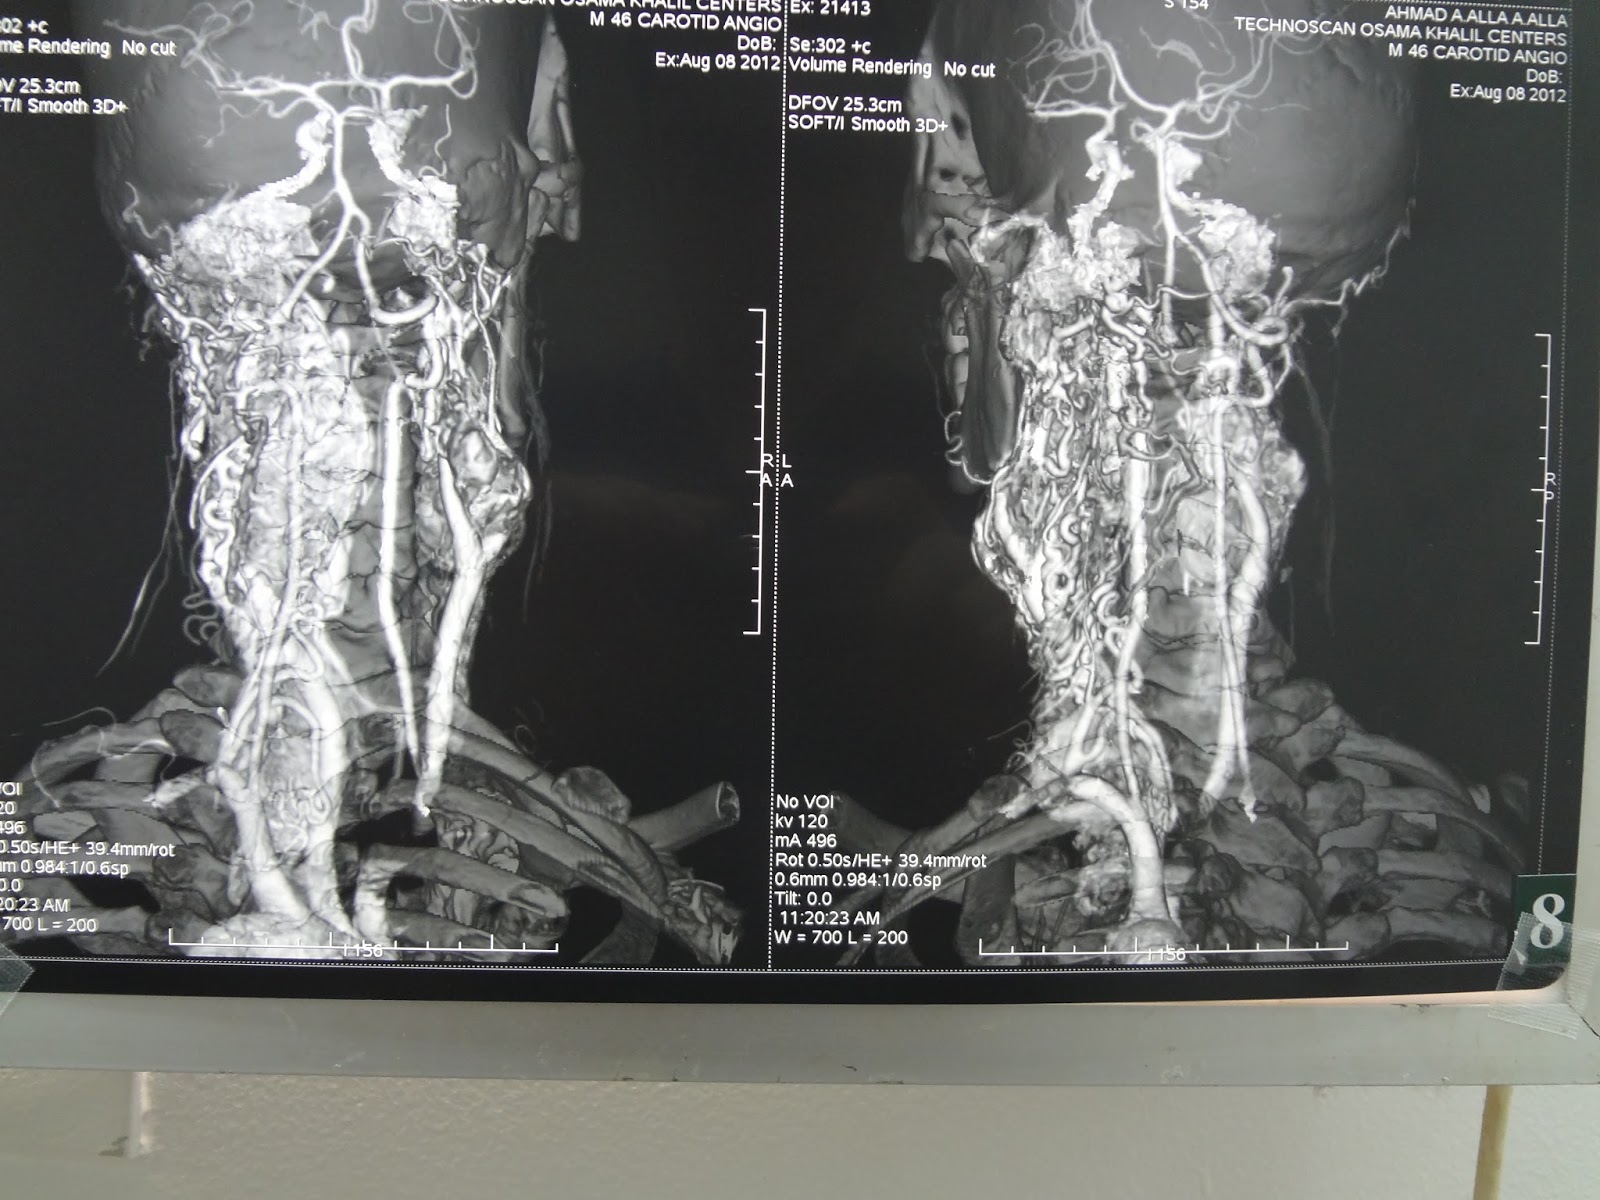

bilateral glomus vagale tumor, CT multislice carotid angiograghy 64 row detector

male patient 45 years old has bilateral neck mass in relation to carotid arteries

scanned with ct carotid angiograghy which detect bilateral hypervascular neck swelling

which excised on one side only and send for HPE and reveal a glomus vagale tumor.